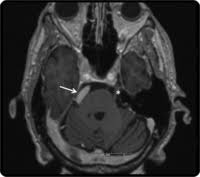

Vp shunt fracture. Ventriculoperitoneal vp shunts are a device used to shunt cerebrospinal fluid in the treatment of hydrocephalus. In follow up examinations we retrospectively reviewed patients who underwent revision surgery. Peritoneal catheter fractures occur most commonly in the neck the area where the tube is subject to mechanical stress.

The rate of shunt complications 1 month following insertion is 15 rising to 25 after 1 year and reaching 34 after 5 years 39 fig. Evidence based approach to complication prediction and avoidance during shunt surgery vp shunt surgery has a considerable long term complication rate. The shunt tubing is fractured at the level of the upper cervical spine.

Between 2006 and 2016 vp shunt surgery was performed on 1357 pediatric patients in our clinic. 5 6 the typical presentation of a fractured shunt system is usually quite late after initial insertion and it may be marked by the rapid onset of dramatic symptoms such as headache nausea swelling over the shunt tract often in a location over the shunt fracture or it may occur in a more subtle fashion over a longer period of time. As the name suggests a catheter is placed with its tip in the ventricle.

In follow up examinations we retrospectively reviewed patients who underwent revision surgery. The distal tubing is now coiled within the abdomen. Disconnection and fracture are two significant mechanical vp shunt dysfunctions and must be adequately researched and understood even during routine follow ups.

We have discussed the diagnosis and treatment approaches in patients with discontinued disconnected or fractured ventriculoperitoneal vp shunts that caused mechanical dysfunction. A disconnected or fractured shunt may be working and it is not safe to state that the shunt is no longer needed. Frontal radiograph of the cervical spine edge enhanced shows a fracture of the ventriculo peritoneal shunt drainage tube black and white arrows with caudal retraction of the distal fragment.

Between 2006 and 2016 vp shunt surgery was performed on 1357 pediatric patients in our clinic. 28097382 indexed for medline mesh terms. Ventriculoperitoneal vp shunt complications include blockage and infection early and prompt detection of shunt dysfunction is vital as delay can lead to markedly raised intracranial pressure coning and death.